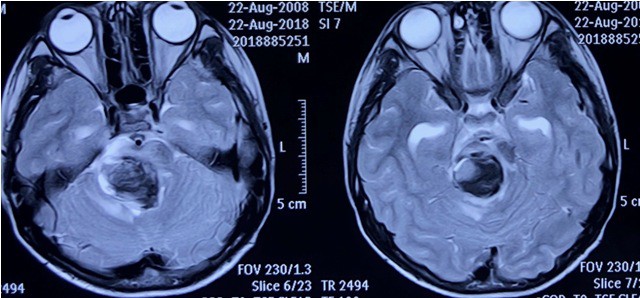

Phim chụp cộng hưởng từ khối u thân não chảy máu ở bệnh nhân.

ThS.BS Nguyễn Thanh Xuân – Phó Trưởng khoa Phẫu thuật Thần kinh I, BV Việt Đức cho biết, ngày 21/8/2018, bệnh nhân vào viện trong tình trạng lơ mơ, chậm chạp, bị liệt chân tay, mạch chậm, được chẩn đoán là một khối u mạch lớn ở thân não chảy máu, dẫn đến tình trạng bệnh diễn biến nặng nề.